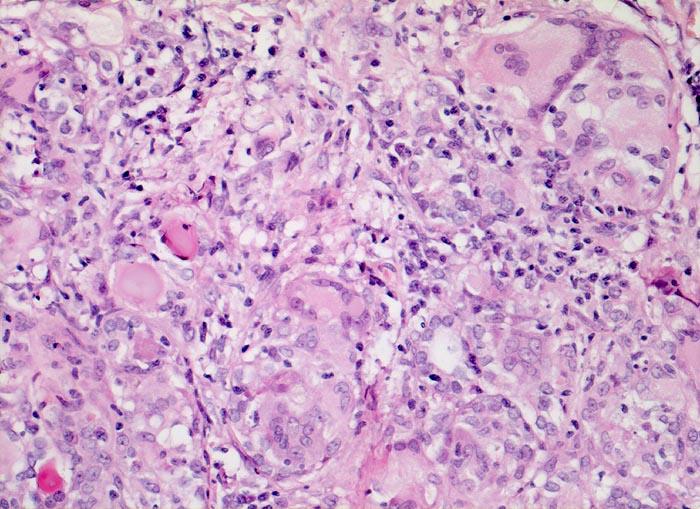

AP/ Subakute Thyeroiditis de Quervain

Subakute Thyeroiditis de Quervain

Schilddrüse